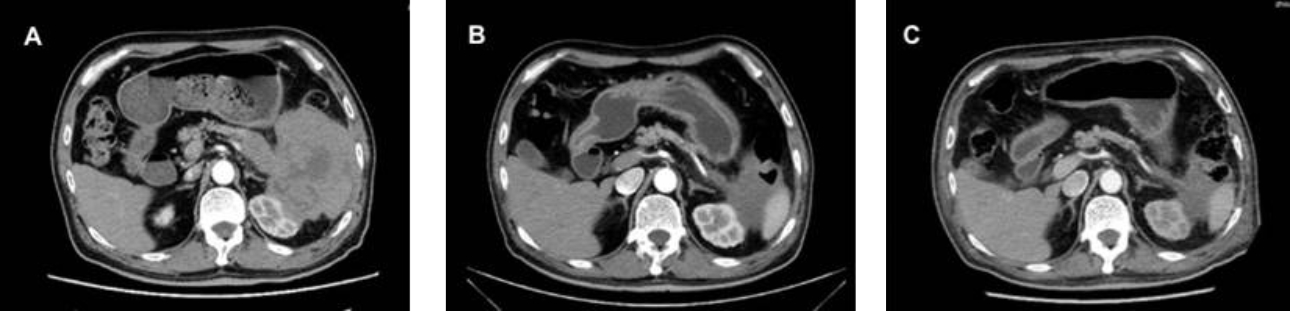

??? ?????? R-Hyper-CVAD-A ????? ???? ??? CT ??? ?? ?? ??? ??? ??? ?? ?? ? ? ????. (Fig 4 A-C). ??? ???? ??? ?? ??? ??????.